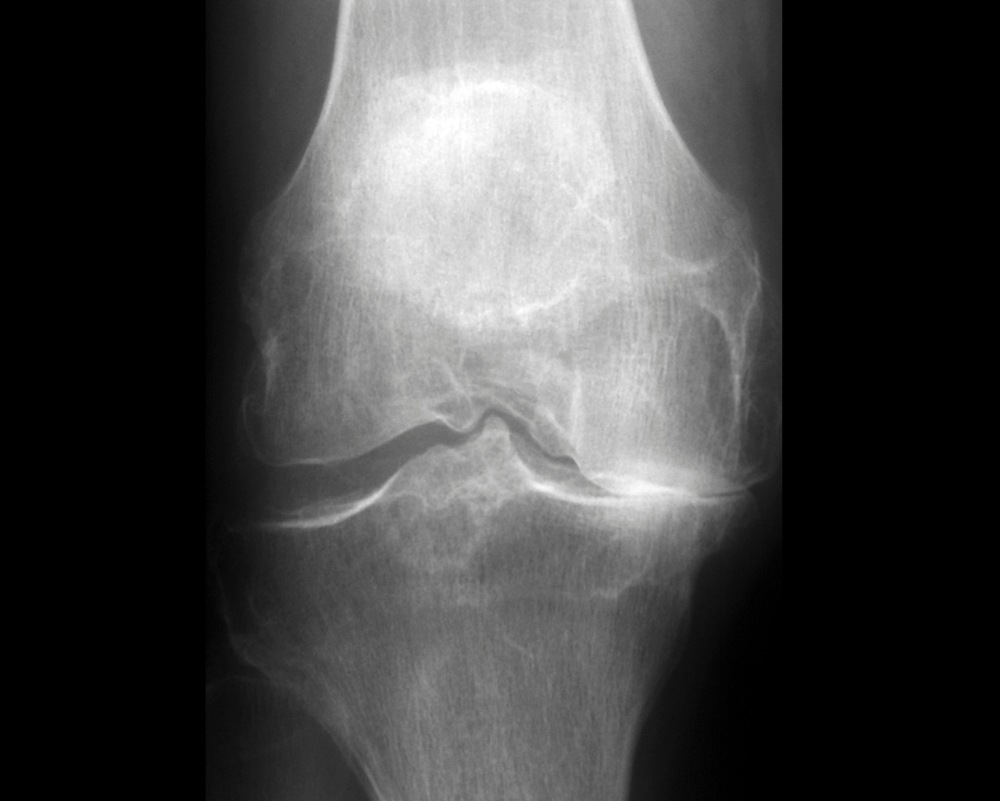

If needed, Dr. Mehta will arrange further tests, such as X-rays or MRIs, for a clear picture of your knee’s health to better guide treatment.

If needed, Dr. Mehta will arrange further tests, such as X-rays or MRIs, for a clear picture of your knee’s health to better guide treatment.

Knee Arthritis

Arthritis wears down knee cartilage, causing stiffness, pain, and limited movement.

Dr. Mehta’s personalized approach helps ease pain and improve flexibility so you can enjoy daily life.